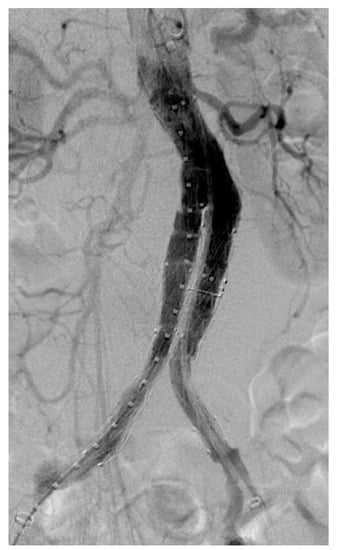

EVAR procedures were all performed with Medtronic Endurant® according to the manufacturer’s instructions for use (IFU); type of anesthesia, surgical or percutaneous access, and need for adjunctive intraoperative procedures (i.e., sac embolization and/or patent aortic branches embolization) were tailored for each patient (Figure 1).

Figure 1.

Intraoperative angiography showing complete aneurysm exclusion after Medtronic® Endurant implantation.